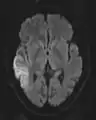

The most common application of conventional DWI (without DTI) is in acute brain ischemia. DWI directly visualizes the ischemic necrosis in cerebral infarction in the form of a cytotoxic edema,[18] appearing as a high DWI signal within minutes of arterial occlusion.[19] With perfusion MRI detecting both the infarcted core and the salvageable penumbra, the latter can be quantified by DWI and perfusion MRI.[20]

DWI showing necrosis (shown as brighter) in a cerebral infarction